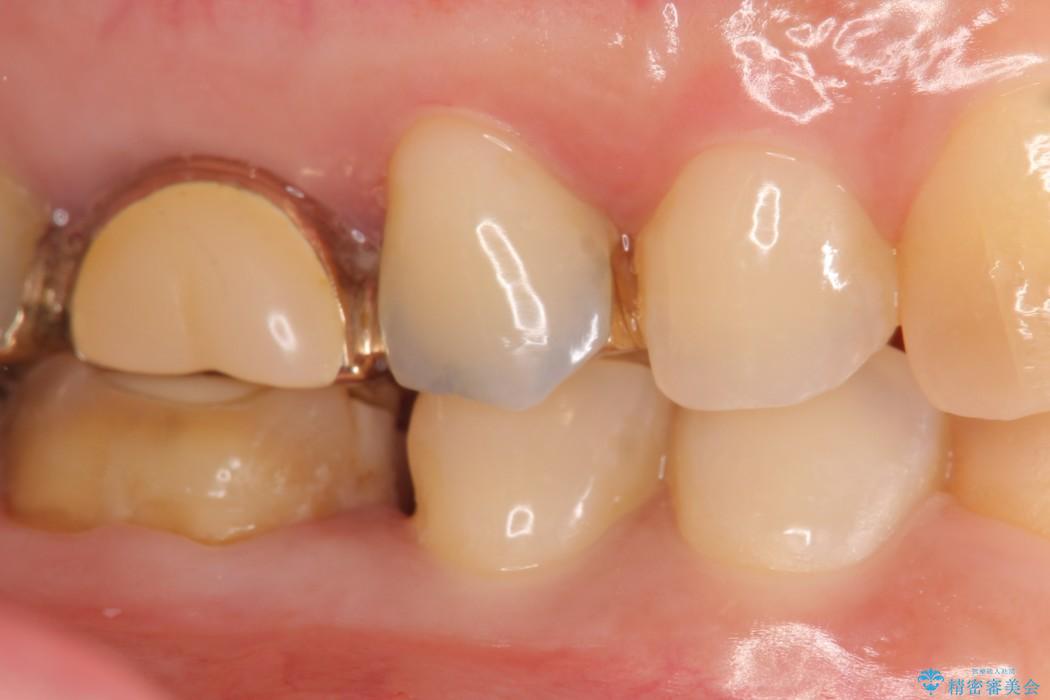

適合不良であるインレーを放置するリスクを患者様へ説明してご納得いただいた上で、オールセラミックインレーで治療を行うこととしました。

そうならないためにも適合の良い剛性にも優れた素材を用いた治療を求められます。特にセラミックが使用されたインレーは見た目が自然なだけでなく適合性、剛性共に高い水準を持つためリスクを減らすことができます。

しかしセラミックは金属に比べて強い衝撃には弱く欠けたり割れてしまう可能性があるため注意が必要です。